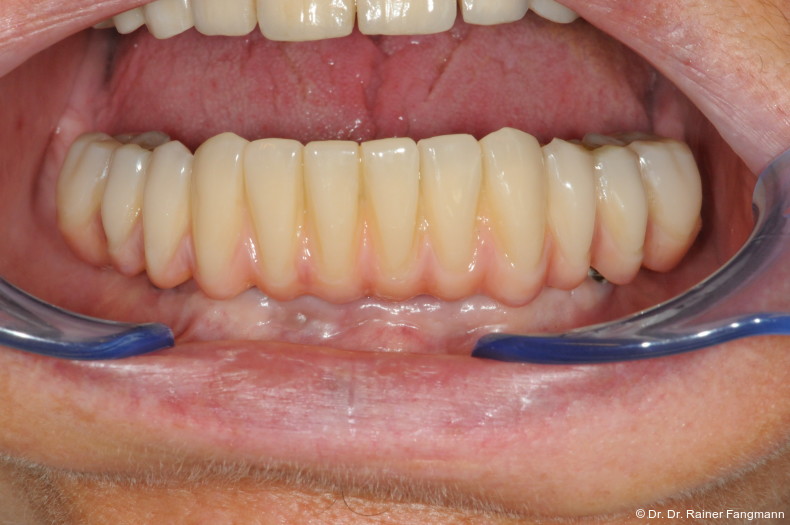

Foto: Dr. Dr. Rainer Fangmann

Die Fragestellung zur Implantatanzahl im Oberkiefer oder Unterkiefer ist oft sehr patienten- und behandlerspezifisch zu betrach-ten. Für Kostenträger ist die Frage oft von übergeordneter Relevanz. Für den Praktiker stellt sich die Frage nach der Umsetzbarkeit. Zudem sind auch das Knochenangebot und dessen Qualität für die Anzahl der Implantate und auch der Implantattypus maßgebend. Folgender Beitrag zeigt ein Fallbeispiel mit drei Implantaten, sechs Jahre in situ.